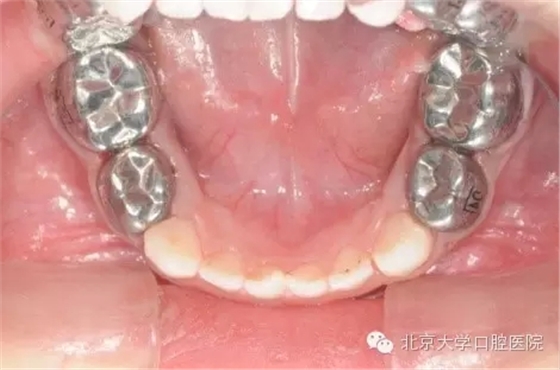

全麻治療中醫(yī)生對(duì)缺損較大的后牙經(jīng)常會(huì)采用“預(yù)成冠”修復(fù)的方法,預(yù)成冠由不銹鋼制成,可以很好的恢復(fù)牙齒的外形并預(yù)防牙齒及充填體折斷,并不影響牙齒替換。